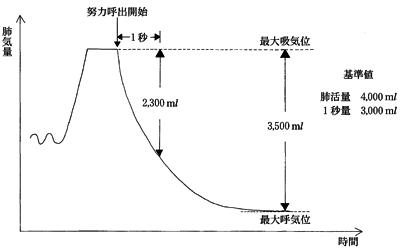

45歳の男性。息切れで階段を昇れなくなったため受診した。スパイログラムで図のような計測値と努力呼出曲線とを得た。この患者の呼吸理学療法の目的はどれか。